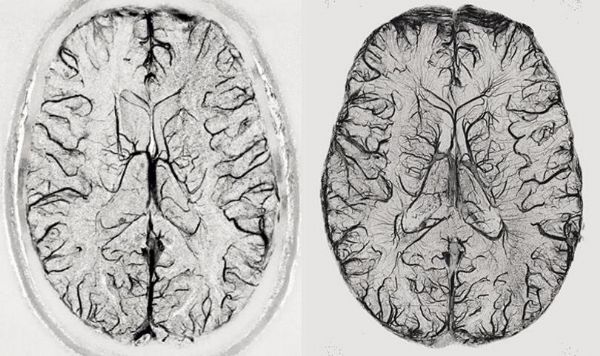

超高场(磁场强度)成像仪的吸引力是显而易见的,然而磁场越强,其信噪比越高,这意味着对物体的成像分辨率更高或成像速度更快。在3T时MRI成像仪能够解析1毫米大小的大脑结构,而在一台7T强度的成像仪下该分辨率就能达到0.5毫米,这就足以识别人类大脑皮层内部的功能单元,或许还能够观察到人类大脑中神经元连接之间的信息流,而具有更高场强度的成像仪预期的分辨率至少是7T设备的两倍以上。

较好的分辨率也是喜忧参半的,因为其会使得成像仪对轻微的运动变得高度敏感,而一些由呼吸或心跳引起的机体重复运动或许也是可以被模拟或移除的。研究者Menon说道,最大的挑战就是7T甚至更高,这种强度目前在较低分辨率的成像仪中并不存在。如今7T强度的成像仪能通过揭示小于1毫米的结构来为研究人员开启研究人类活体大脑的新视野。

在被揭示的结构中有6层大脑皮层,3毫米厚得到大脑外层区域主要负责人类高水平的认知能力,而且每一层都非常特殊,一种负责处理来自大脑其它区域的信息输入,一些则进行信息处理并将处理结果传递到大脑的其它部分中。如今成像仪的强度跨越到7T能够让研究人员测定不同大脑皮层的相对活性,进而就能阐明大脑信息的传递机制,这或许就是3T或1.5T成像仪时代的巨大进步,正常情况下我们提及A和B相连接时,我们只知道其具有相关性,但却并不知道信息之间是如何流动的。

研究人员希望能对人类大脑的柱状组织进行深入研究,大脑的皮层柱结构被认为会发挥计算的能力,同时还会对特殊的刺激优先产生反应,比如物体的方位等;虽然仅有500微米大小,但皮层柱垂直于大脑皮质层,且能通过中间层来进行互相通信,如果成像仪能在柱状水平下测定大脑的活性,那么科学家们就能够对单个神经元的计算得出结论,这将会让人非常激动,因为磁共振成像仪的一个局限性就是其无法直接测定大脑的神经活性。

7T磁通量的成像仪能够更好地帮助测定大脑的连接性,研究人员旨在完全绘制出大脑神经元间的连接,如今他们利用3T和7T的成像仪对184名个体进行了扫描,相比3T而言,在7T磁通量下,研究者能够检测到神经元之间的沟通以及较多的神经网络,这或许对于未来研究人员准确预测人类疾病至关重要。